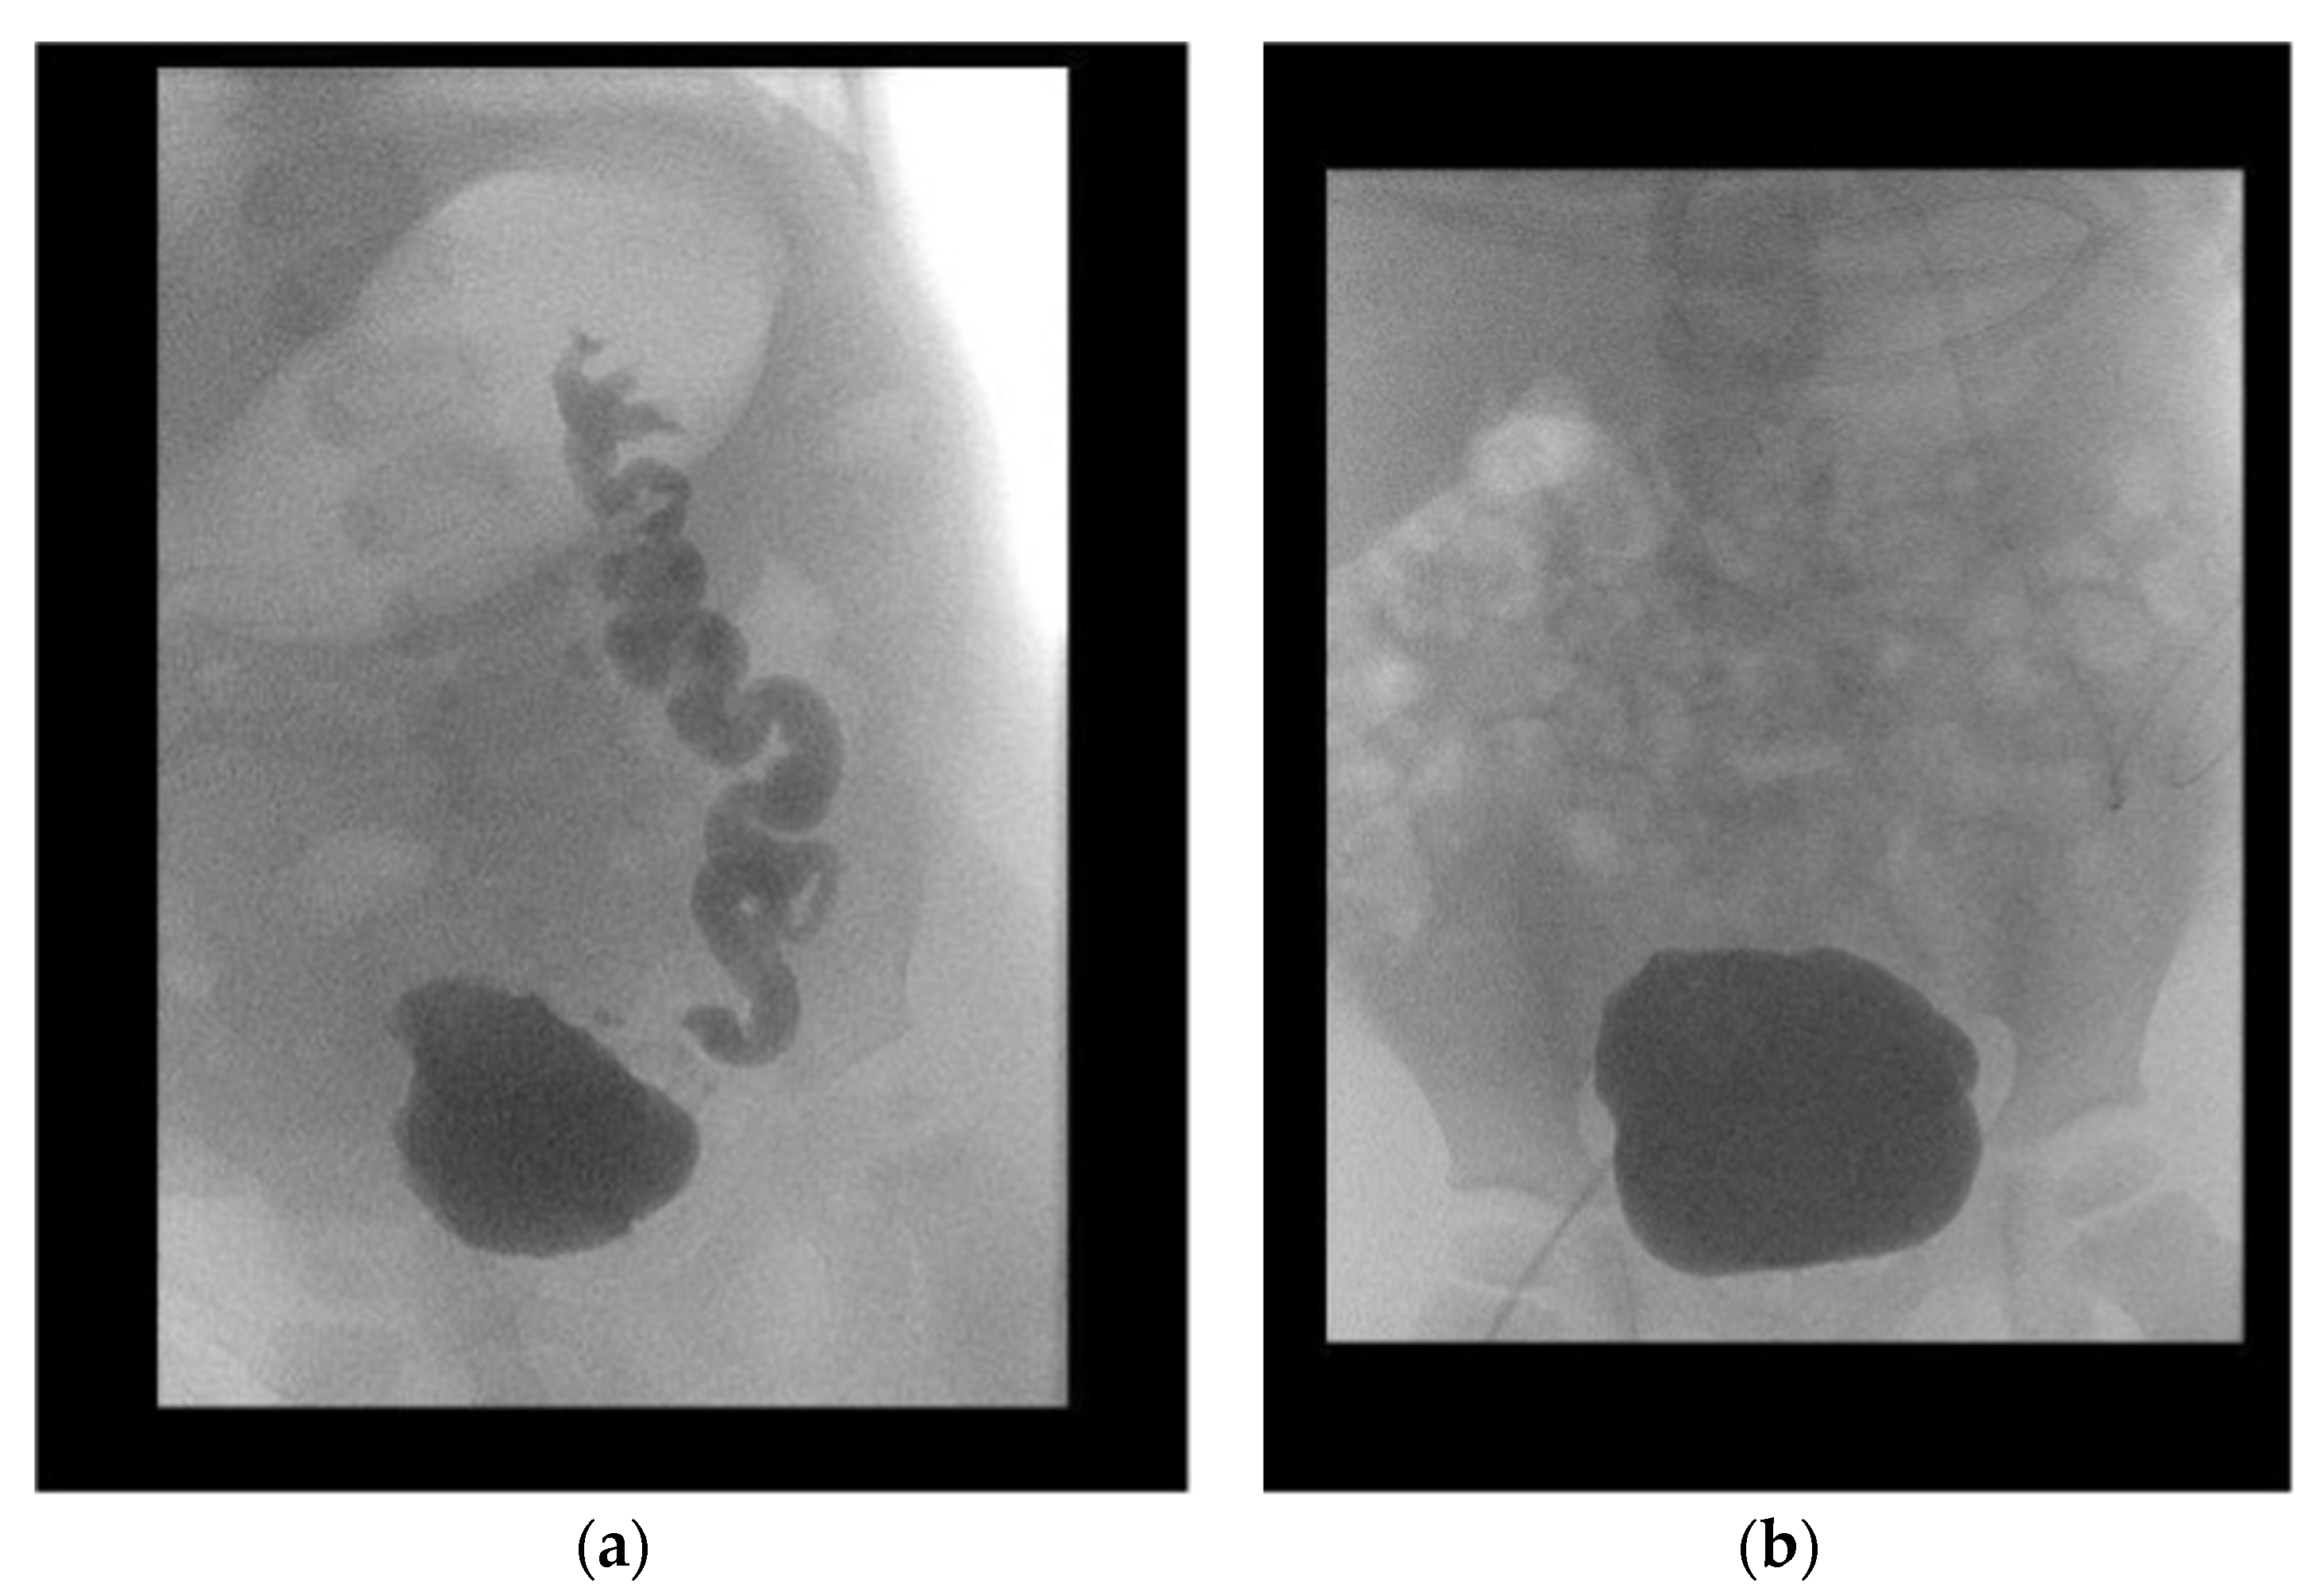

All patients were followed-up after a median period of 64.5 months (IQR 36.0–97.25). Initial VUR on the contralateral kidney was present in eight patients. Two patients showed persisting VUR after surgery: one patient in the subsequently transplanted kidney, the other in the contralateral dysplastic kidney, which additionally caused recurrent urinary tract infection. Overall, the median decrease in the SWRD score was 1.5 (from 4.5 (range 2–7) to 3.0 (range 1–5)) (p = 0.147) (Figure 3). The mean age-adjusted bladder capacity increased from 77% (±0.28) before UCP to 102% (±0.46) (p = 0.139) after UCP, resulting in a 1.3-fold enlargement of the bladder.

Figure 3. Pre- and postoperative voiding cystourethrograms of one patient (a,b). Preoperatively, severely trabeculated bladder and vesicoureteral reflux (a). Normalization of bladder configuration and decrease in vesicoureteral reflux at 1-year follow-up (b).